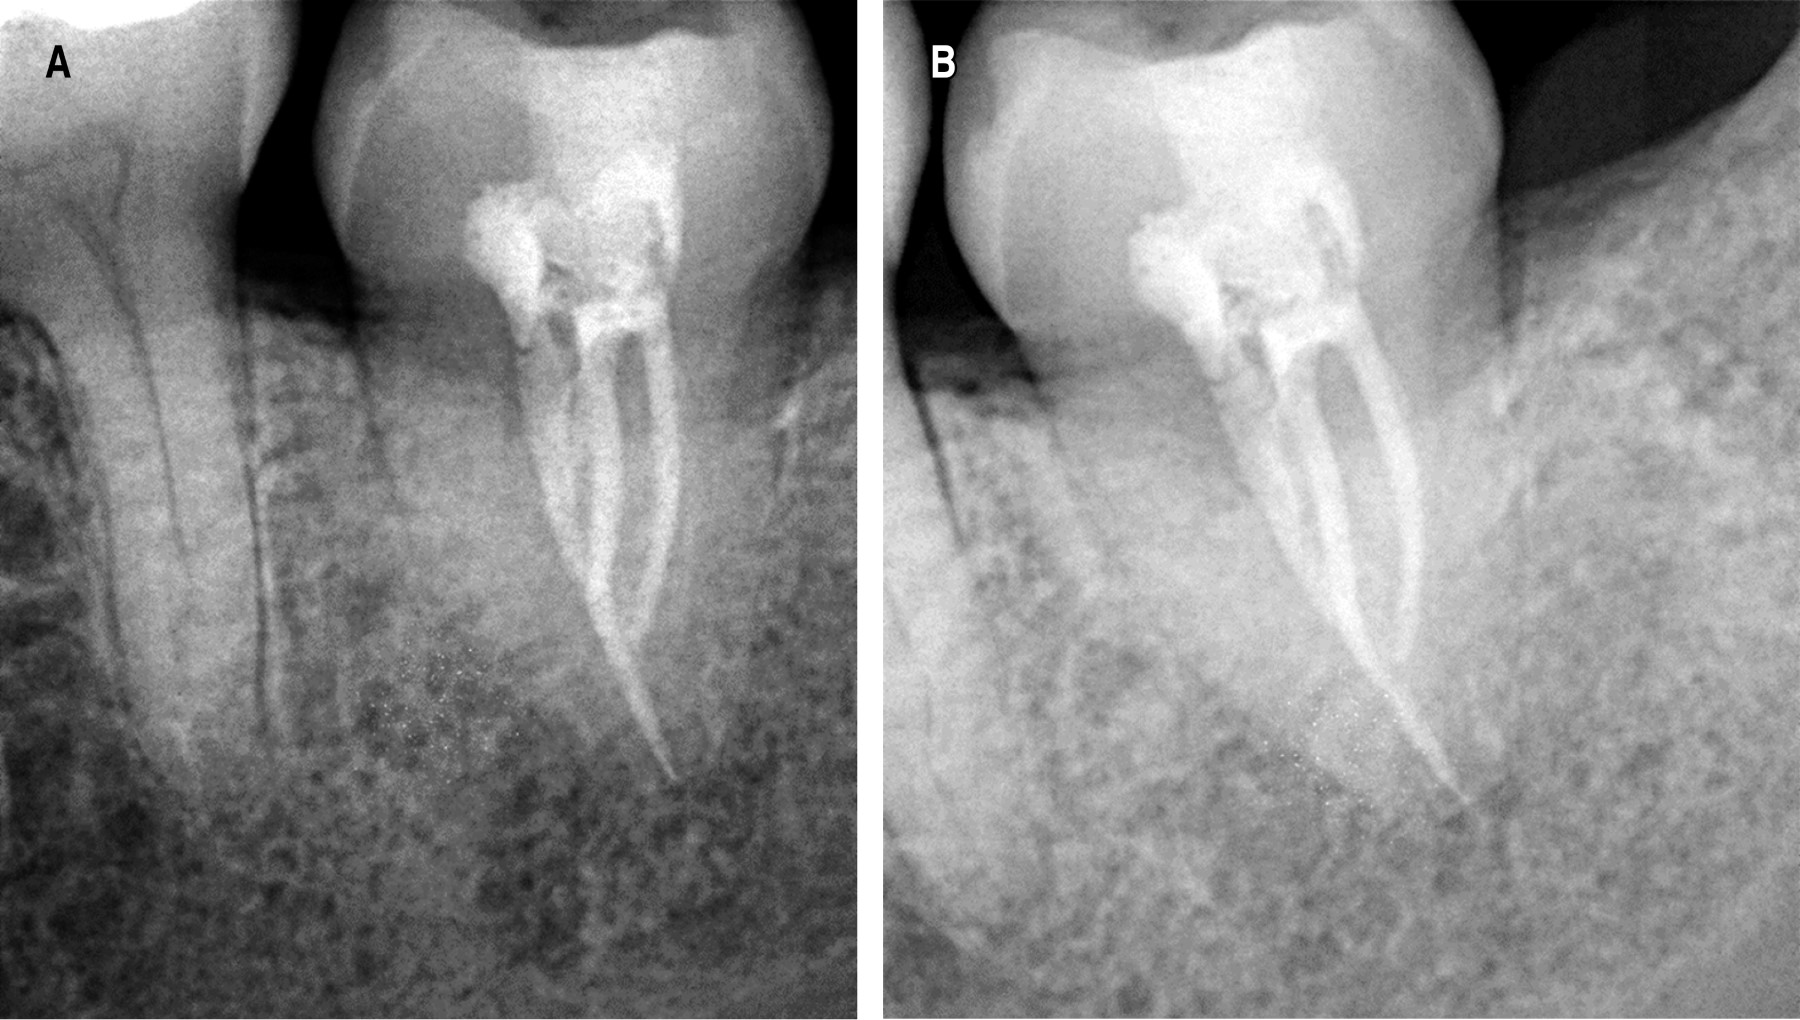

Se trata de paciente femenino de 19 años de edad, sin antecedentes médicos conocidos, quien acudió a nuestro servicio para valoración y tratamiento por presentar pérdida de sustancia calcificada a nivel coronal de OD 3.7 y 3.8. Al momento de la evaluación clínica del paciente se observó la presencia de los OD 1.8 y 2.8 y resto radicular de OD 2.5, 3.7, 3.8 y 4.8 (Figura 1A y B).

Posterior a la segunda semana del autotrasplante se realizó un primer control postoperatorio (Figura 6A). El paciente acudió con el especialista en endodoncia para realización del tratamiento de conducto con la colocación de hidróxido de calcio el cual se mantuvo en los conductos radiculares hasta el primer mes de postoperatorio, realizando así el control radiográfico (Figura 6B).

Posterior a la colocación del hidróxido de calcio, se realizó la obturación definitiva del diente autotrasplantado con gutapercha y su posterior control a los tres meses (Figura 7A), hasta su control de los seis meses (Figura 7B).